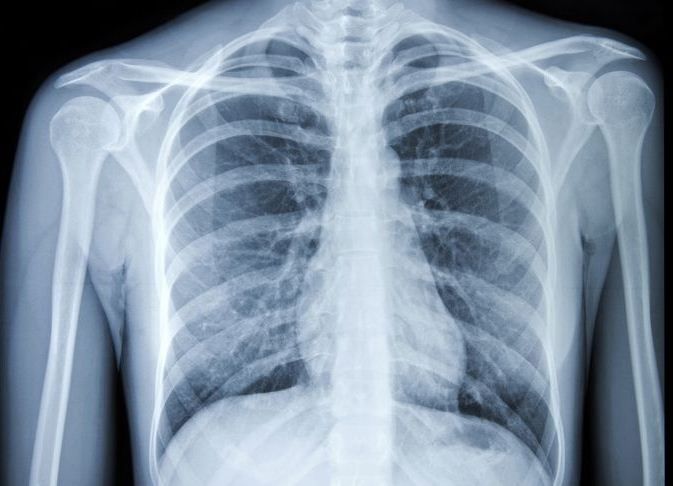

Pemeriksaan rontgen dada merupakan pemeriksaan foto sinar-X pada dada untuk mendapatkan informasi mengenai ukuran, bentuk, kontur, dan lokasi anatomi jantung, paru-paru, pembuluh darah besar (aorta, arkus aorta, dan arteri pulmonaris), serta tulang-tulang pada dada (tulang servikal, thorakal, klavikula, dan tulang iga). Perubahan pada struktur jantung, paru-paru, atau pembuluh darah bisa menunjukkan adanya suatu penyakit atau kondisi tertentu.

Foto sinar-X menggunakan pancaran energi elektromagnetik yang tidak terlihat untuk menghasilkan gambaran tulang dan organ-organ tubuh bagian dalam pada kertas film.